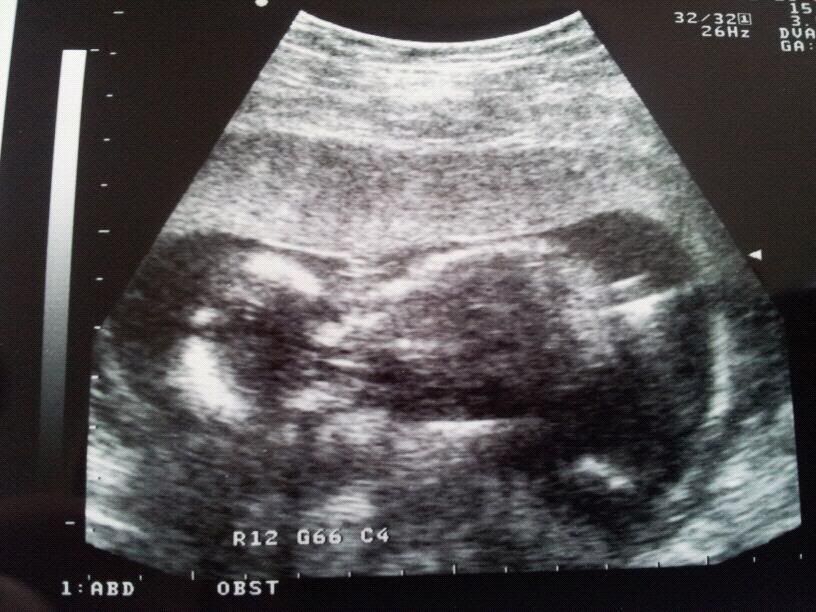

vanmiddag dus voor de extra echo geweest. er was meteen een prachtig kindje in beeld! alles er op en er aan! het lag heerlijk met opgetrokken beentjes en de armpjes op de borst, duimpje in de mond. heerlijk aan het slapen. hartje klopte mooi, en het lag heerlijk te kroelen. mama is helemaal in love! helaas zorgde deze positie er wel voor dat het onmogelijk was om te zien of het nou een jongen of een meid was. vk zij op een gegeven moment wel dat het er als een echte meid uit zag haha! maargoed, dat wachten we nog even af tot de 20 weken echo. alles is dus goed met onze wurm. gelukkiger kan deze mama in spé er niet van worden!

dan mijn vleesboom... deze was bij de 10 weken echo 1,5 cm groot. vk heeft er toen afdrukken van gemaakt en in mijn dossier gedaan. vandaag is die ook uitgebreid nagekeken, hij is nu 6,5cm groot. dat betekend dus dat ie 5cm gegroeit is... er zit dus wel groei in, wat mij dus niet geruster maakt... maargoed, voor nu is alles goed en heeft de kleine er geen last van. mijn echo bij de gyn staat voor 14 maart, das over drie weken dus dan word alles nog een keer volledig onderzocht met behulp van 3d echo's enz.

hier nog even de echo die ik mee krijg, hoop dat jullie er wat van kunnen maken ;-)